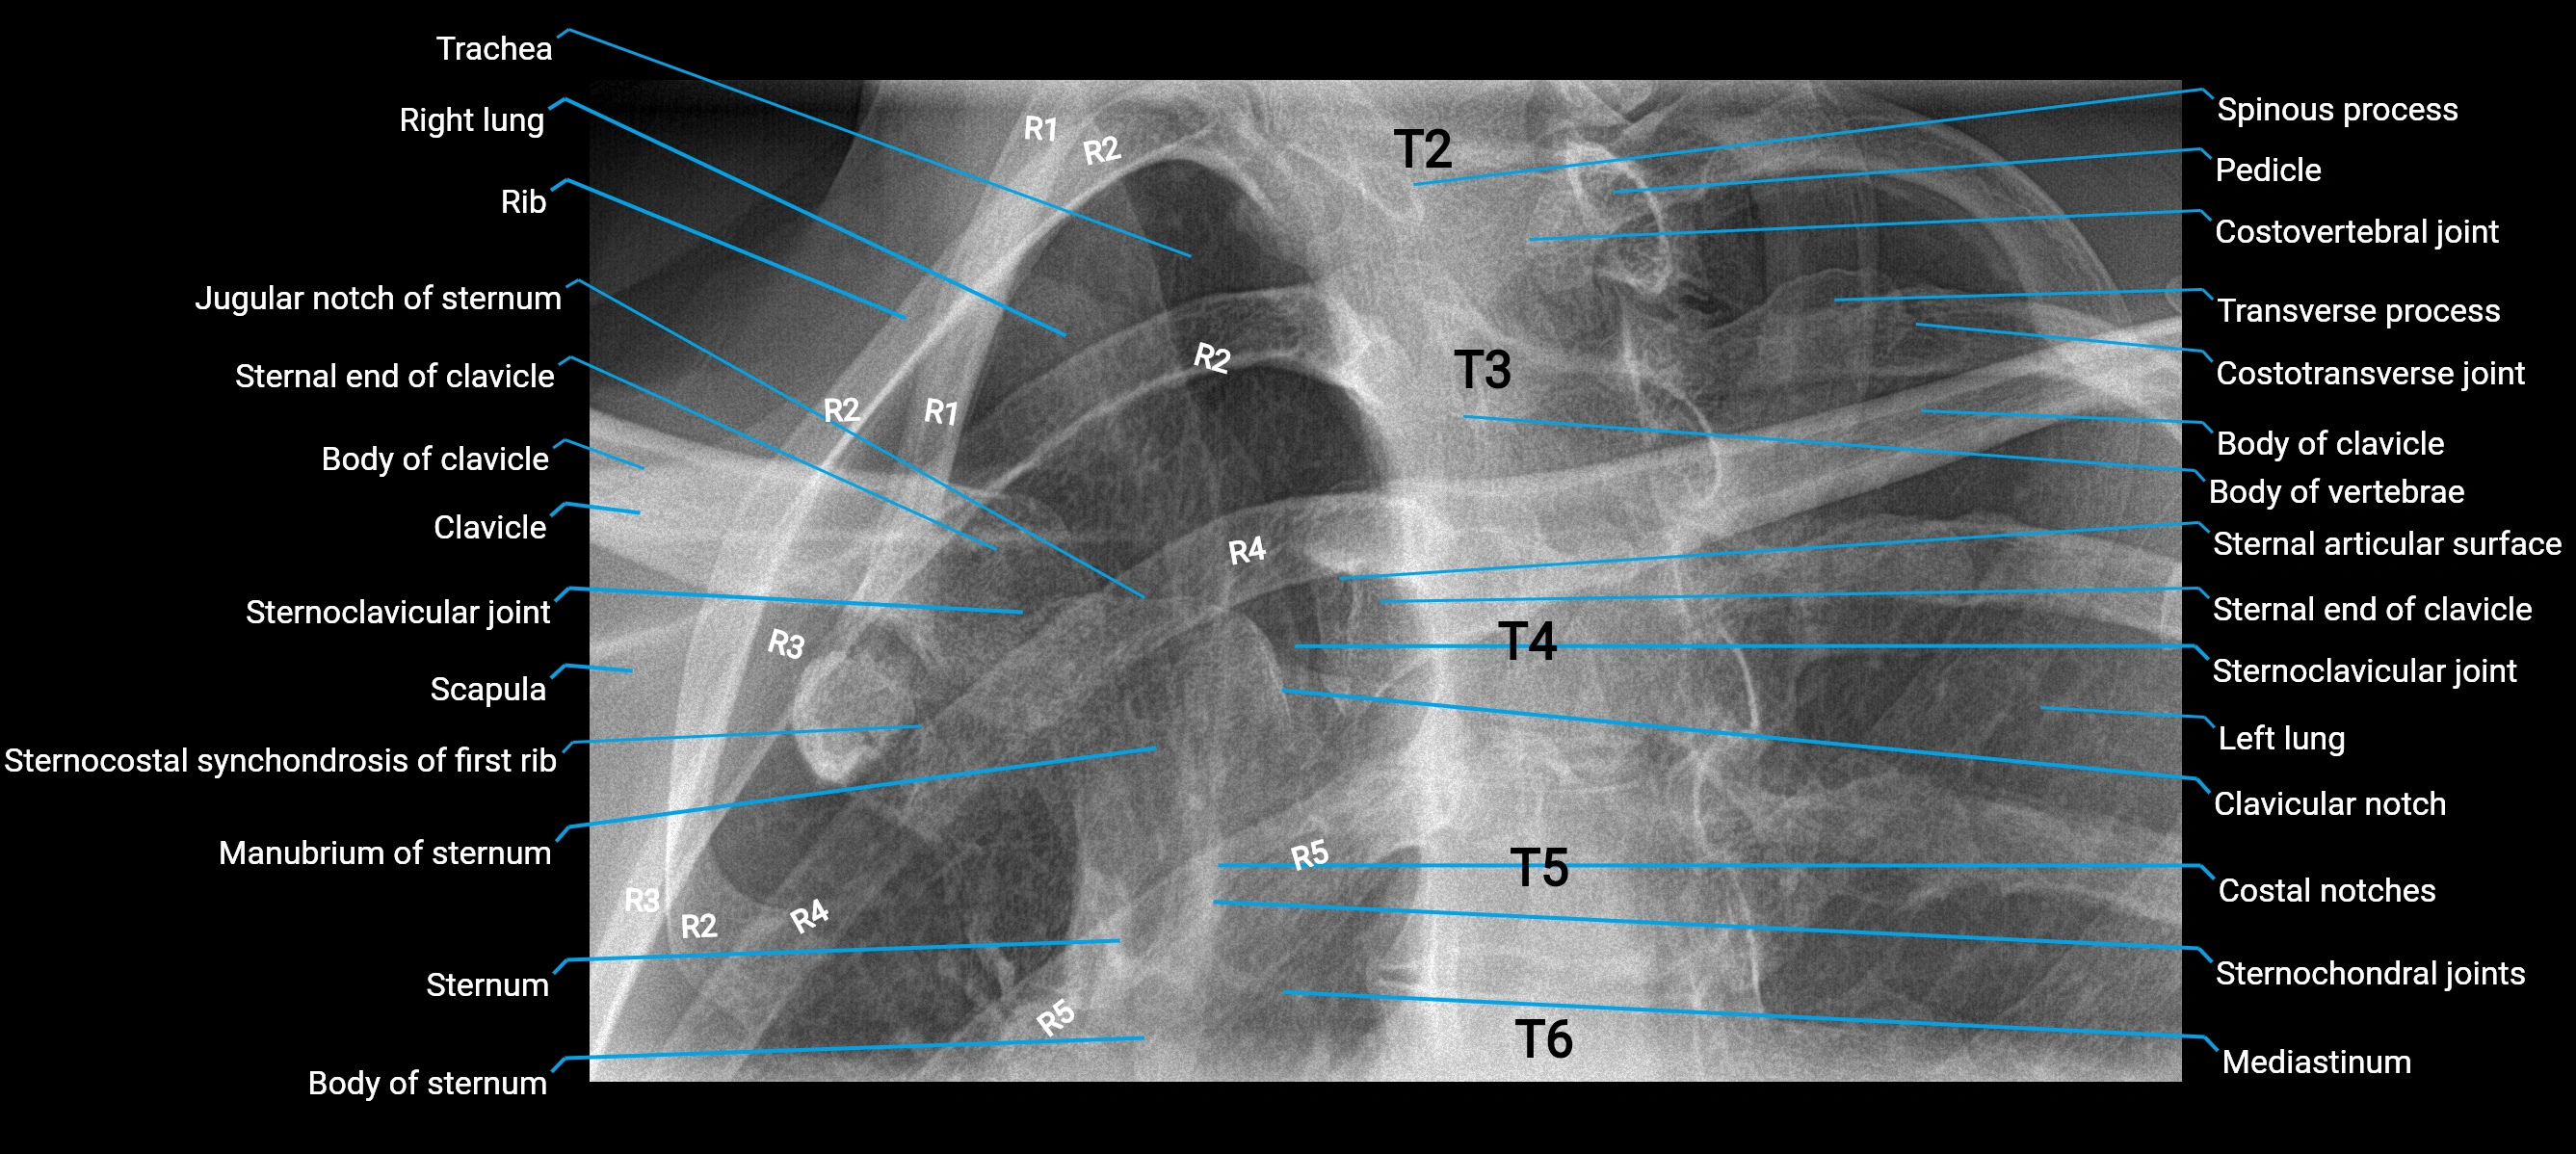

Chest radiograph (PA view):

• Aortic knob: Smooth, rounded convexity along the left upper mediastinal border

• Margins: Well-defined and continuous

• Position: Above the left hilum

• Size and contour: Influenced by patient age, body habitus, and aortic orientation